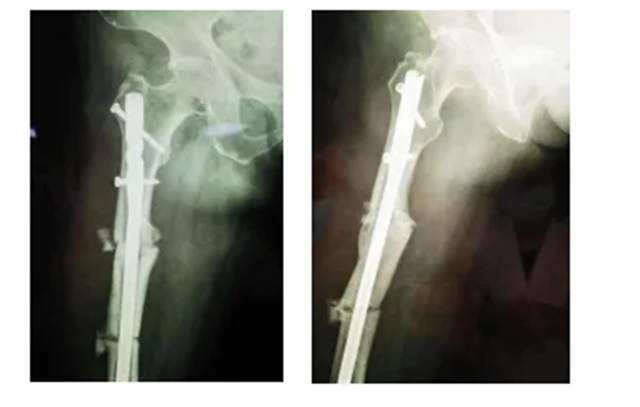

(股骨中段断裂,上端有明显畸形)

当她的X光片出来时,收治的医生都被她的伤情吓了一跳。原来此次她骨折的上端还有一处骨伤畸形愈合。这是什么情况呢?

据汪永泉主任介绍,此次手术很成功,术后通过观察,病人目前没有血管的危象,而且整个神经没有牵拉,而且病人整个下肢体长度,也基本达到术前预想的恢复长度。

术后拍摄的X光片

但因张女士属于股骨上段骨折畸形以后手术归正,整个股骨头的负重区已经发生了一些改变,髋关节关节炎也可能存在,因此张女士还需进行后续的康复性治疗和护理。